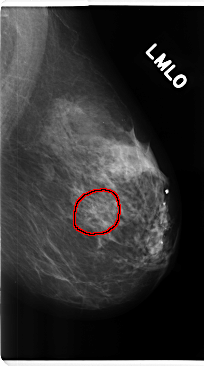

FILE: C_0226_1.RIGHT_MLO.OVERLAY

TOTAL_ABNORMALITIES 1

ABNORMALITY 1

LESION_TYPE MASS SHAPE ROUND MARGINS SPICULATED

ASSESSMENT 5

SUBTLETY 5

PATHOLOGY MALIGNANT

TOTAL_OUTLINES 1

BOUNDARY